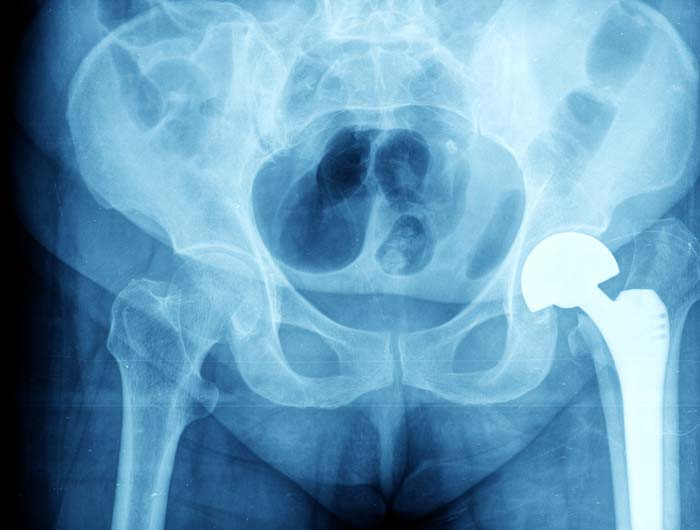

Hip replacement is a very effective way of removing the pain from an arthritic joint for the long term. The type of hip replacement that you receive depends on your age and level of function, as wel..